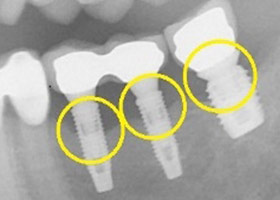

2. 治療前X光片,骨頭嚴重吸收。